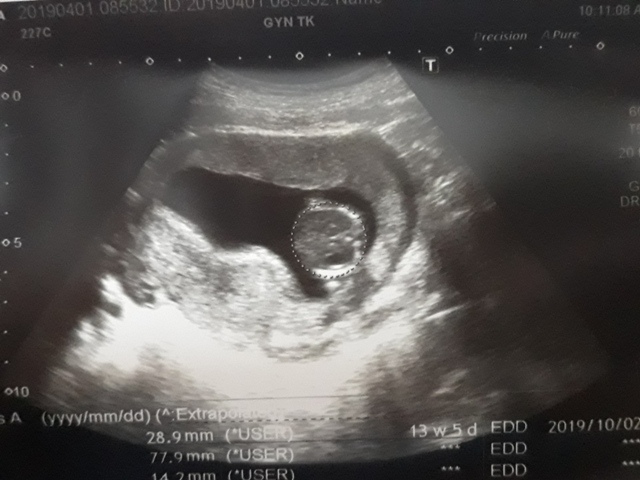

| 2019年04月01日 | 28.9mm | 77.9mm | 14.2mm | 107g | 153 |

| BPD:胎兒頭骨橫徑 AC:胎兒腹圍的長度 FL:胎兒大腿骨的長度 EFW:胎兒的體重 | |||||